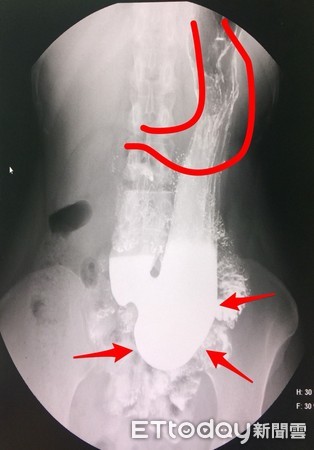

▲紅色畫線區為胃原本的位置,如今卻下垂骨盆腔。(圖/錢政弘醫師提供)

除此之外,剛生產後的婦女,習慣吃飽後,就馬上激烈運動、走跳的上班族,也都有胃下垂的情形,這些患者在X光顯影下,原本應該要在肚臍上方的胃,已拉長下垂到骨盆腔附近,更容易造成食物在胃中囤積,難以被排入腸道中好好消化吸收。